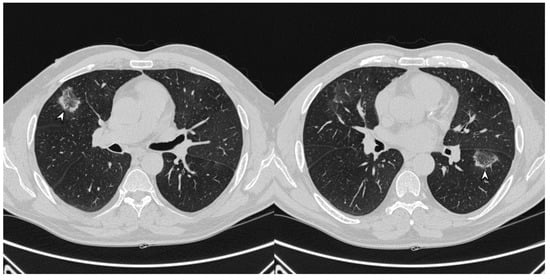

Figure 5. Fibrotic pattern: bilateral sub-pleural reticulations (arrowheads) and architectural distortion, clearly visible in peripheral regions of right lung (a) and left lung (b).

1.3.4. Progressive Fibrosis Pattern

OP can produce sub-pleural basal reticulations and architectural distortion in about a 15% of cases, mimicking the appearance of nonspecific interstitial pneumonia (NSIP); the reticulations coexist with regions of consolidation or appear later (Figure 5) [24]. This presentation seems to be associated with a poor outcome [26]. As reported by OIkonomou et al., this pattern may occasionally result in honeycombing and must be differentiated from usual interstitial pneumonia (UIP) [20]. Pathologically, alveolar epithelial damage is a common condition in both OP and UIP. In OP, the necrosis of alveolar epithelium is followed by the migration of fibroblasts from the interstitial compartment to airways, while, in UIP, fibroblastic foci are restricted to interstitium, and intraluminal fibrosis is less extensive than in OP [20].